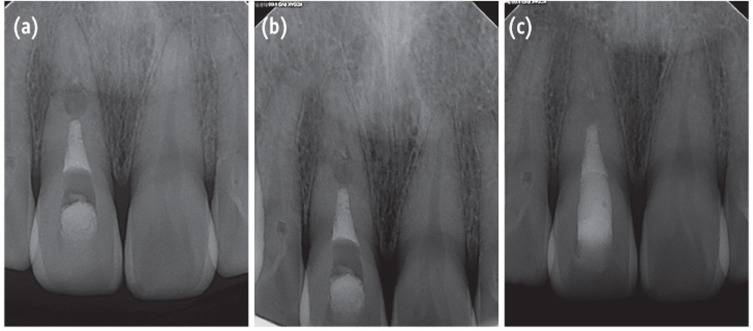

A 33-year-old man presented to the Department of Conservative Dentistry at the Wonkwang University Dental Hospital (Iksan, Korea) with a complaint of discomfort of the maxillary right central incisor during mastication. Two days before, the tooth had impacted against a rigid object. The patient's medical history was noncontributory. Radiographic examination showed a horizontal fracture in the middle third of the root of the tooth and a slight displacement of the apex (Figure 1a). Intraoral examination revealed that all maxillary teeth had normal responses to pulp vitality tests, no mobility, and no discolored crown. Since the maxillary central incisor showed no signs of mobility or pathology, the patient was followed up without any splint appliances. His occlusion was checked and adjusted to eliminate loading on the traumatized tooth during function.

Four weeks after the trauma, a radiolucent area appeared intra-canally on the apical portion of the coronal fragment and it continued to progress until 6 weeks of observation (Figures 1b and 1c). Root canal treatment was initiated on the coronal fragment with K-file and irrigated with 5% sodium hypochlorite. Working length was established with an apex locator (DentaPort ZX, Morita, Kyoto, Japan). Special care was taken to instrument within the coronal fragment. After 2 months of intracanal calcium hydroxide dressing, the canal was obturated with mineral trioxide aggregate (MTA, ProRoot, Dentsply, Tulsa, OK, USA) (Figure 2a).

In Case 1, internal resorption around the coronal fracture line was observed at approximately 4 weeks after the trauma. Andreasen et al. reported 3 types of resorption in patients with root fractures, (1) external surface resorption (ESR), (2) internal surface resorption (ISR), and (3) internal tunneling resorption (ITR).1 Andreasen stated that these root resorption processes are usually correlated with healing processes and therefore require no interceptive treatment. The pathogenesis of internal root resorption and subsequent healing following root fracture result from an interplay between the exposed dentin, a damaged but uninfected pulp, and the in-growth of vital tissue.1,7 In Case 1, the ISR type of root resorption was apparent on radiographic examination at approximately 4 weeks, and therefore a process of healing was expected. Root canal treatment was unfortunately initiated without a full knowledge of the healing process of root fractures. At the 2-year follow-up examination, the tooth showed complete healing on the radiograph. However, the tooth supposedly could have healed spontaneously, even without root canal treatment. For the successful management of root fractures, it is important to understand the healing patterns thoroughly.

Figure 1

(a) The radiograph of the initial visit shows a horizontal root fracture line on the maxillary right central incisor; (b) The 4-week follow-up radiograph shows internal resorption around the fracture line; (c) The 6-week follow-up radiograph shows that the internal resorption site is larger and more distinct.